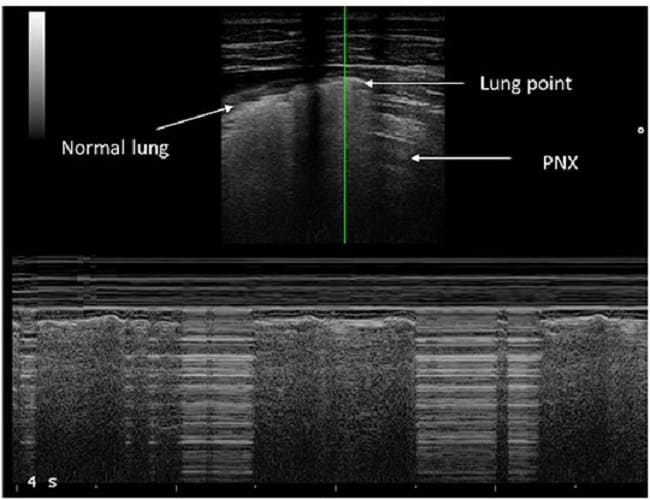

Gambar 4. Pneumothorax pada USG Thorax.

Pada pneumotoraks, dapat menunjukkan gambaran khas, yaitu:

-

Stratosphere sign, yaitu hilangnya gambaran seperti pasir pada M-mode yang harusnya menunjukkan seashore sign

- Gambaran lung sliding tidak ada

- Garis-B/B-lines menghilang

- Terdapat lung point pada M-mode, yang merupakan titik pertemuan antara pleura dan paru yang sehat dengan bagian yang pneumothorax[9,11,12,14]